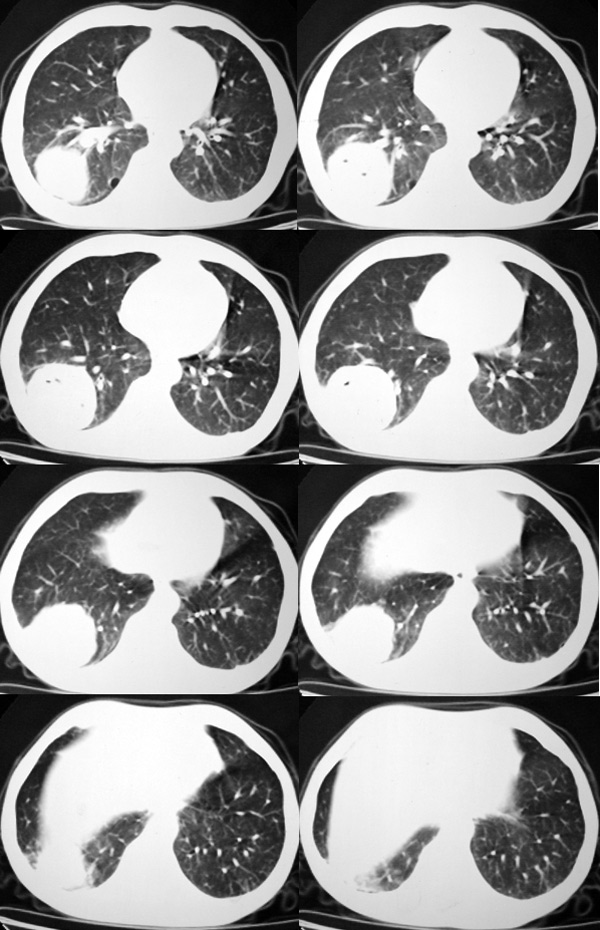

双肺呈毛玻璃状,胸膜旁有多个小囊状气腔。右下囊实性病灶内有园形气体影,边缘光滑,与之相连的胸膜稍增厚,间断发热,抗炎效果不好。考虑机会性感染可能性大。

右下肺占位性病变,其边缘较光整无明显分叶,似有包膜,邻近胸膜无凹陷征及牵拉征象,包块内见数个大小不等气液面及不规则透亮影,纵隔未见明显淋巴结肿大。结合上次ct检查,考虑:炎性包块或真菌感染包块可能性大,周围型肺癌可能性小。

感谢楼主反馈结果。囊实性肿块,壁厚薄不均,壁结节有明显强化,均支持肺癌诊断。